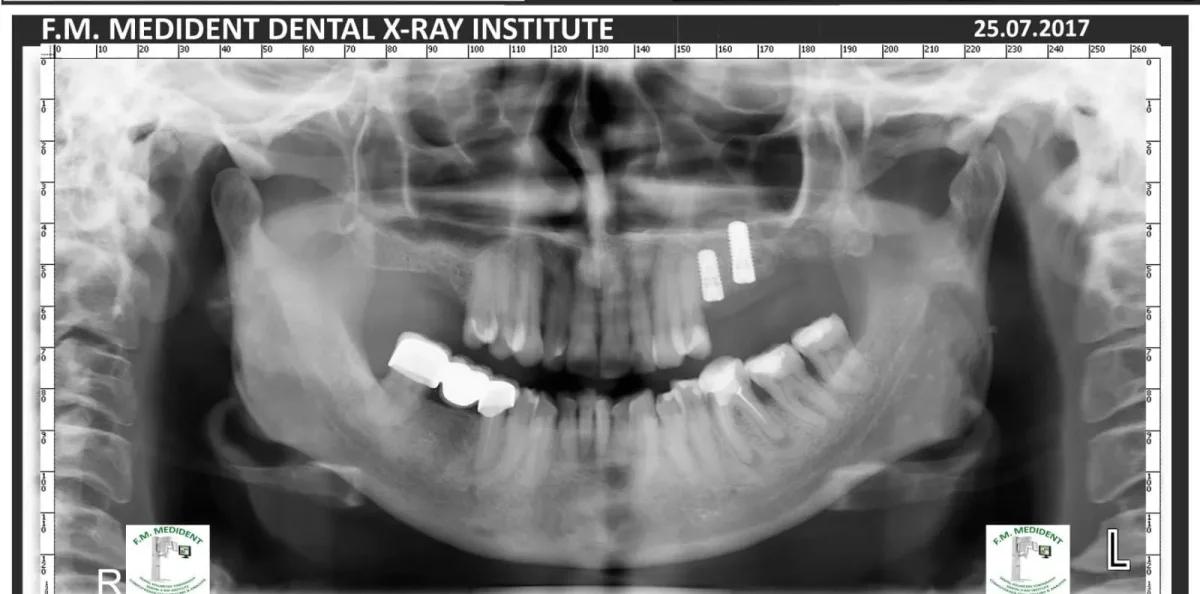

Cazuri reale înainte și după, din tratamente realizate în clinică.

Înainte

După